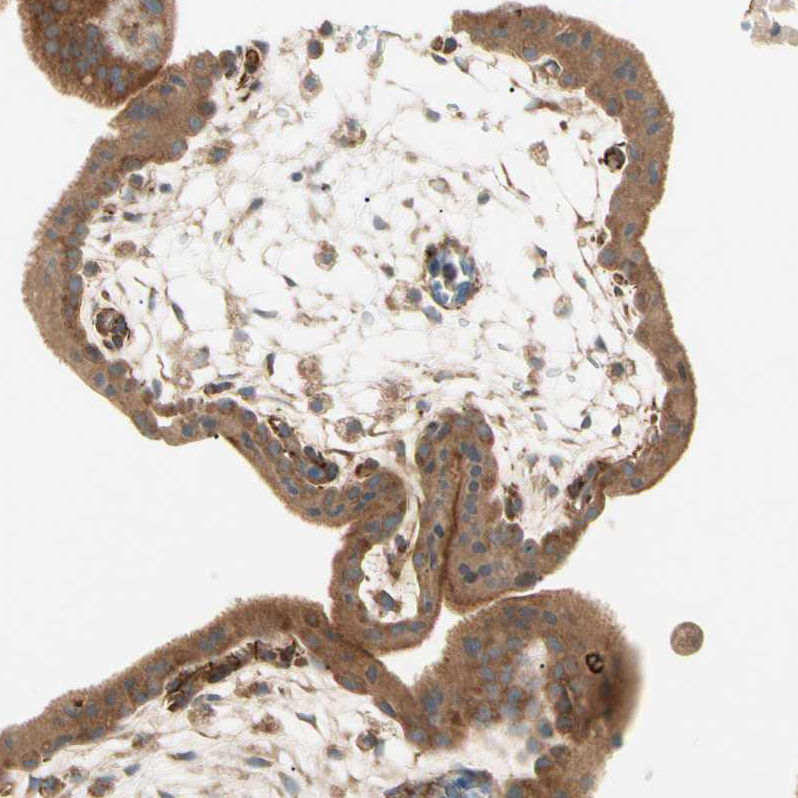

Immunohistochemical staining of human cervix shows strong granular cytoplasmic positivity in squamous epithelial cells.